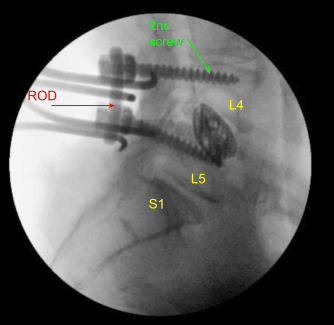

Dada la preocupación por el implante en decúbito prono y nuestra sensación de que las placas terminales pueden haberse fracturado más, expusimos los procesos transversales para L4 y L5 y utilizamos el taladro para crear orificios piloto en el pedículo en el lado izquierdo en L4 y L5. Bajo fluoroscopia, guiamos las sondas a través de los pedículos y golpeamos cada pedículo, luego colocamos tornillos pediculares en L4 y L5.

Estos tornillos fueron estimulados y revisados bajo fluoroscopia, y luego se colocó un montado y se apretaron los tornillos de la tapa. En el lado derecho e izquierdo, decorticamos las facetas y los procesos transversales y colocamos nuestra masa de fusión para la artrodesis.